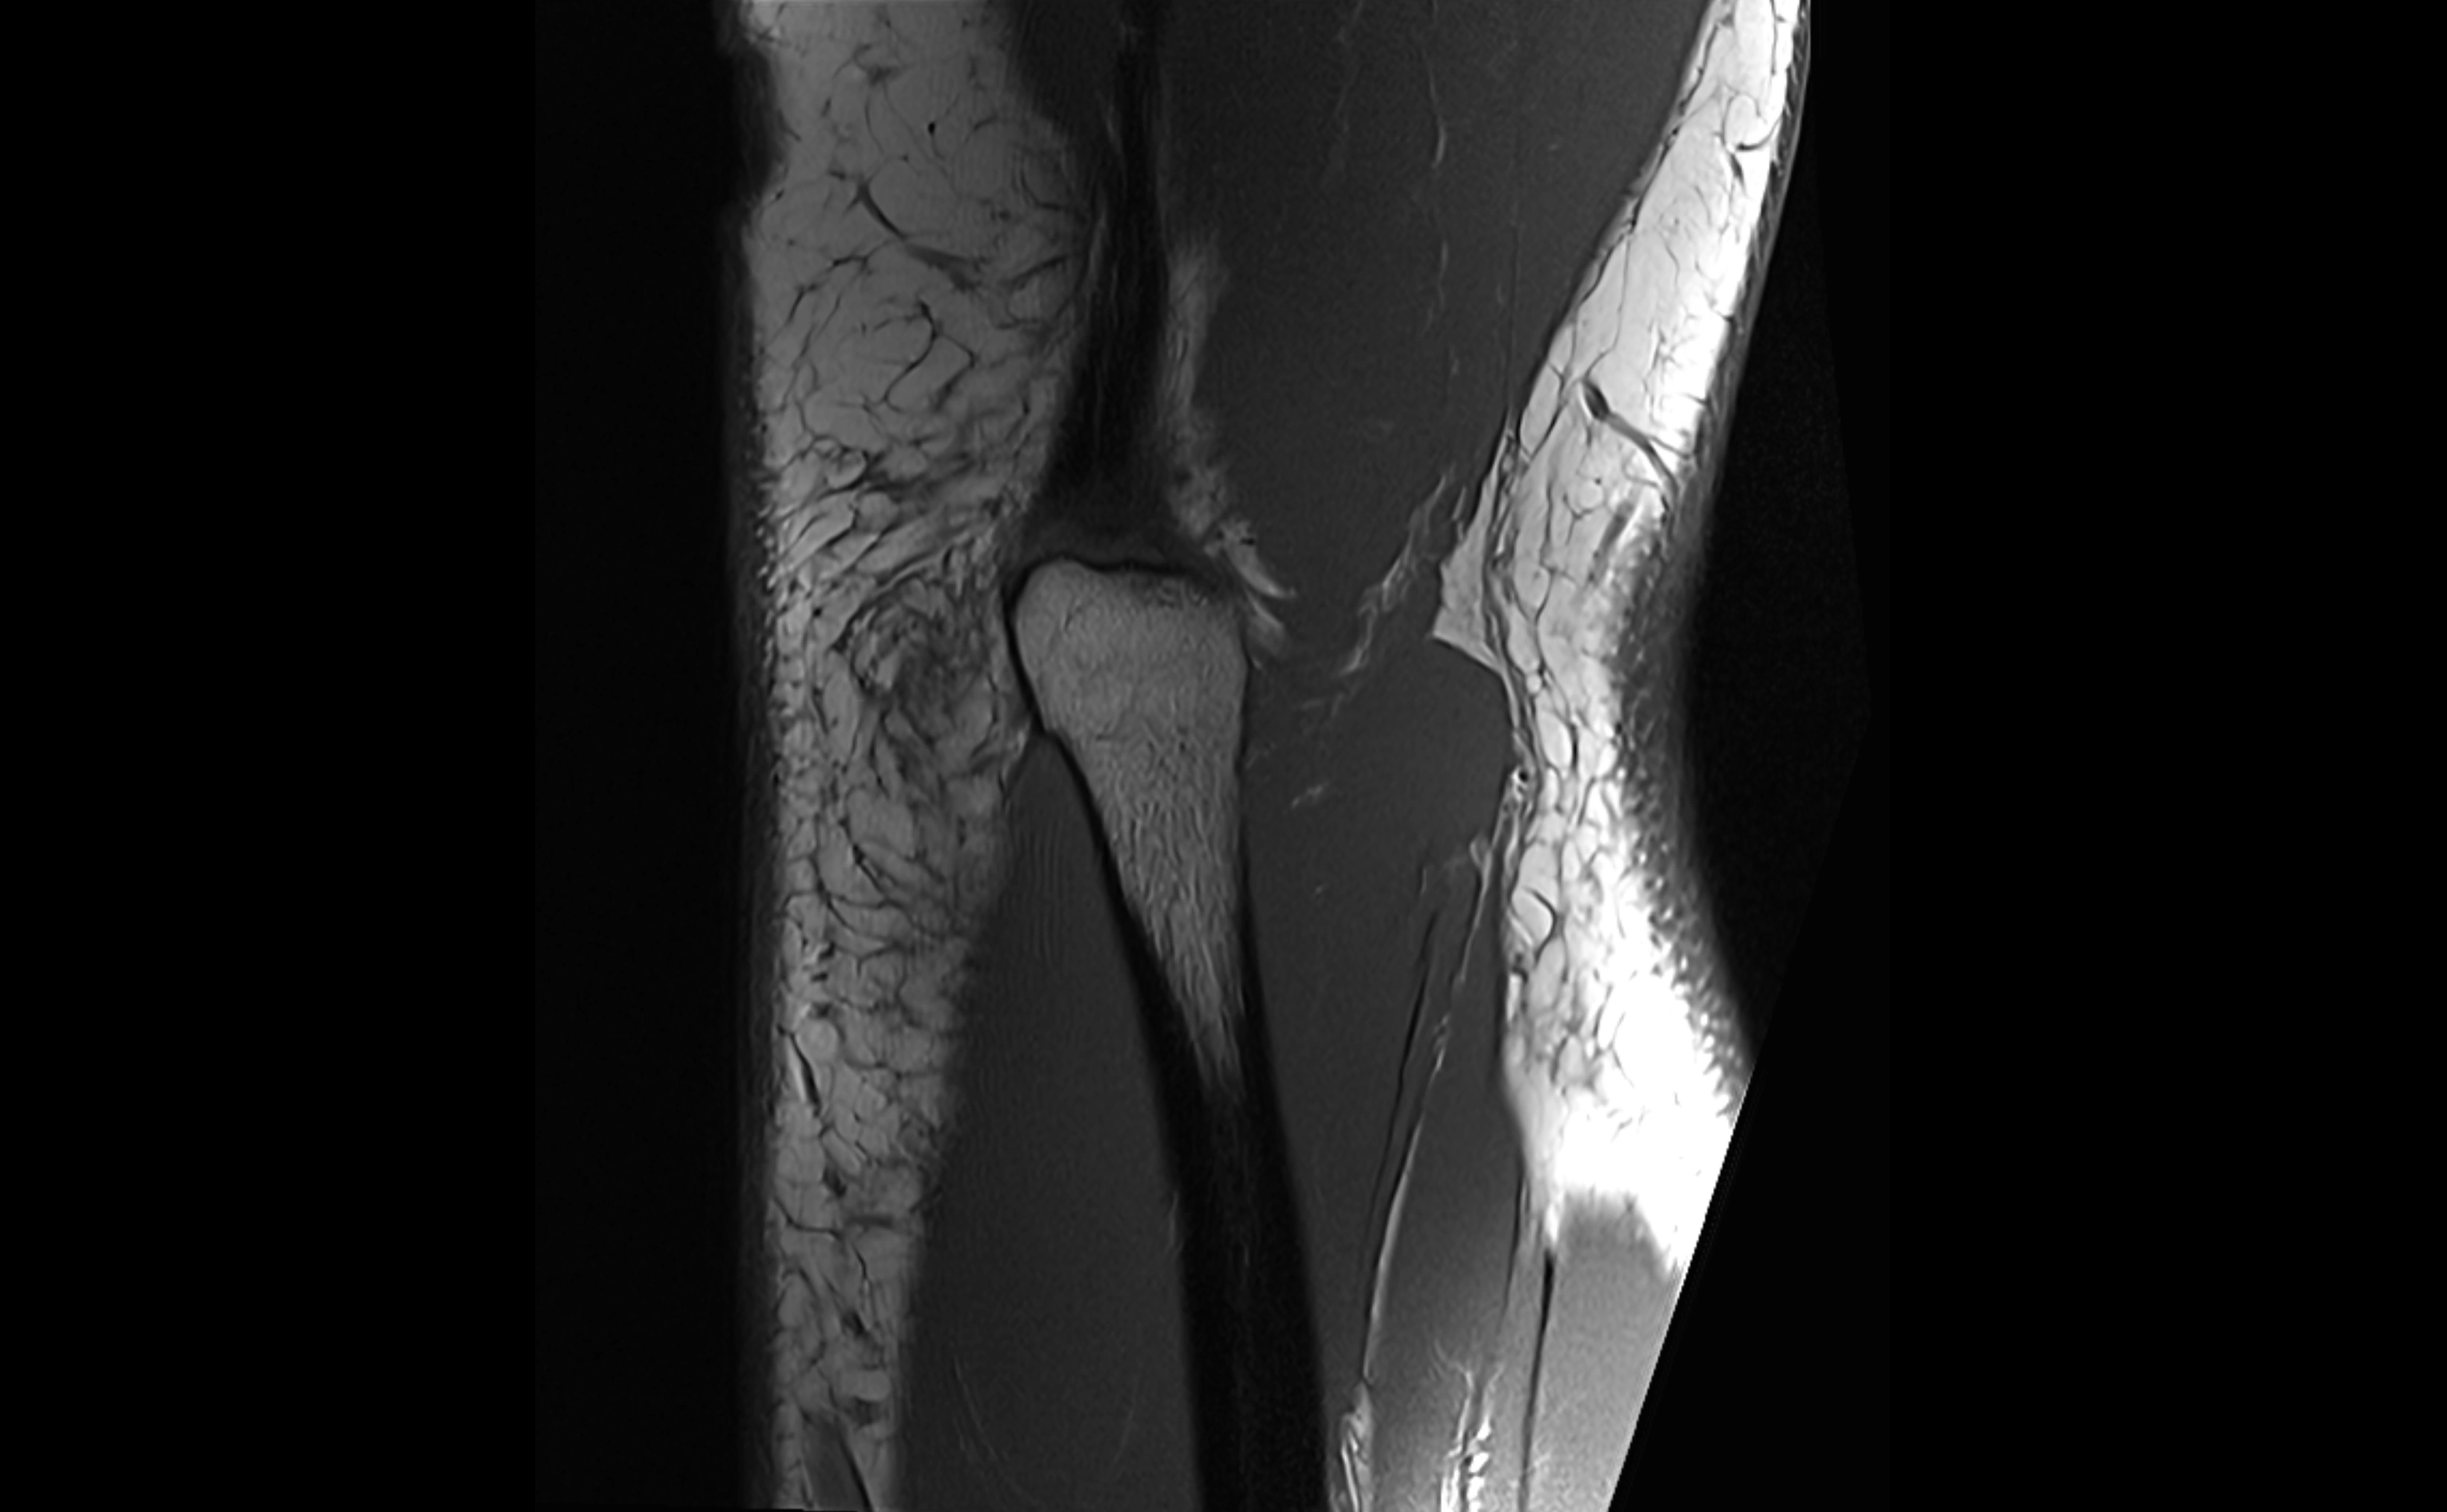

MRI images

image